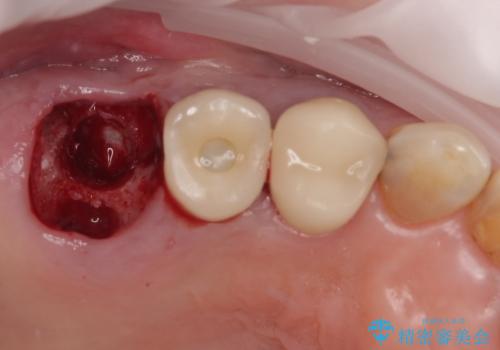

抜歯即時埋入・即時荷重の適応と判断されたため、インプラントによる補綴治療を行うこととしました。

埋入時に十分な安定値が獲得でき、埋入した際に仮歯を装着することができました。

術後の経過は安定しており、抜歯から3ヶ月で治療を終えることができました。